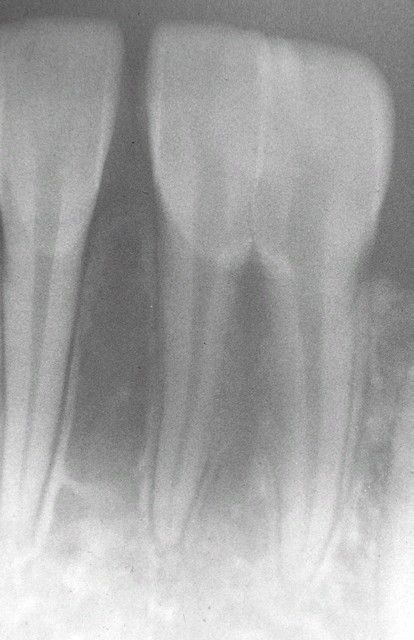

Fusion

Radiographic view of double tooth in the place of the mandibular central and lateral incisors. Note separate root canals